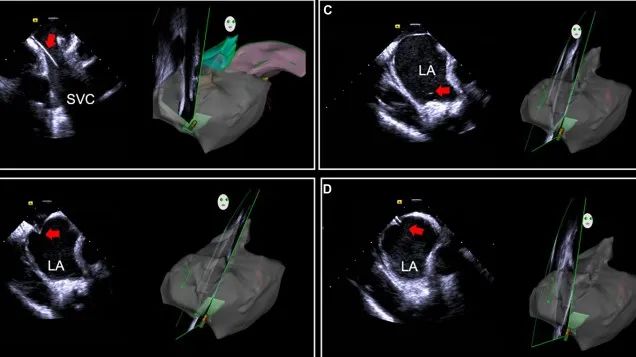

一種與心導(dǎo)管檢查相結(jié)合的超聲心動(dòng)圖診斷新興技術(shù),通過(guò)將超聲探頭置于心腔內(nèi)部,發(fā)射并接收超聲信號(hào),來(lái)精確獲取心臟解剖結(jié)構(gòu)、心臟血流動(dòng)力學(xué)等信息的實(shí)時(shí)成像。與其他影像技術(shù)相比,ICE技術(shù)具有操作簡(jiǎn)單、無(wú)輻射、安全性高、手術(shù)效率高、實(shí)用等優(yōu)勢(shì),ICE在很大程度上有望取代經(jīng)食道超聲心動(dòng)圖(TEE),成為電生理和結(jié)構(gòu)性心臟病領(lǐng)域的理想成像方式。

目前ICE技術(shù)已被應(yīng)用于左心耳封堵、房顫射頻消融、二尖瓣成形、房間隔缺損封堵等多種心臟介入手術(shù),應(yīng)用場(chǎng)景主要圍繞臟電生理、結(jié)構(gòu)性心臟病等領(lǐng)域,目前以電生理應(yīng)用為主。數(shù)據(jù)顯示,我國(guó)結(jié)構(gòu)性心臟病介入器械市場(chǎng)規(guī)模已從2017年的4億元增長(zhǎng)至2021年的20億元,年復(fù)合增長(zhǎng)率達(dá)48.3%;預(yù)計(jì)到2025年,該市場(chǎng)規(guī)模將達(dá)到104億元,可以預(yù)見(jiàn)ICE市場(chǎng)規(guī)模也將同步高速增長(zhǎng),未來(lái)市場(chǎng)發(fā)展空間廣闊。

心腔內(nèi)超聲(ICE)技術(shù)壁壘極高,國(guó)內(nèi)主要廠商核心部件仍舊為進(jìn)口,集成了超聲和圖像處理最前端技術(shù),包括超聲探頭、線纜、軟件成像算法等,是當(dāng)前內(nèi)窺超聲方向最具挑戰(zhàn)的領(lǐng)域。ICE的應(yīng)用經(jīng)歷了2D平面成像、3D三維立體成像、以及4D的實(shí)時(shí)三維立體成像階段。